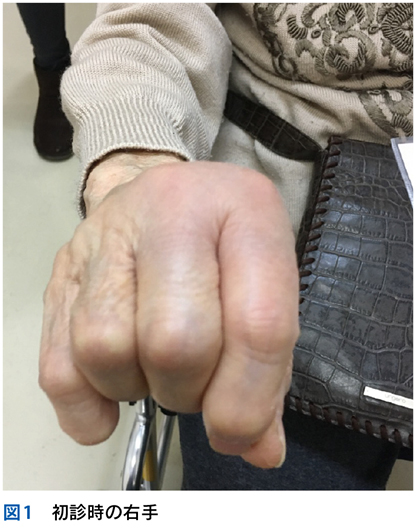

▶ 再びNew England Journal of Medicine誌上の症例検討3)を例として挙げる。40歳代男性が急性多関節炎,下腿の結節性紅斑,両側肺門部リンパ節腫脹を呈したケースである。これら3個の問題の組み合わせは,知っていればLöfgren症候群というサルコイドーシスの1病型と「スナップ診断」できるが,この知識がなくてもフレームの重ね合わせで診断に至ることが可能である。

▶ これらの問題はそれぞれが比較的high yieldであり,よいフレームとなりうる。3つのフレーム内でそれぞれ網羅的に鑑別を挙げ(その方法はステップ②で後述),重なるところに着目するとサルコイドーシスが診断の第一仮説に浮上する。ちなみにこのケースでは患者は発熱と失神も呈しているが,発熱はlow yieldであり鑑別を減らすのに役立たず(急性多関節炎,結節性紅斑,肺門部リンパ節腫脹を呈する疾患はほぼすべて発熱を呈してもおかしくない),失神はこのケースでは最終的に(心サルコイドーシスに起因するものではなく)発熱下での神経調節性失神という評価となり,サルコイドーシスの診断においてはノイズだった(二元論で説明される症状だった)ことがわかる(図7)。